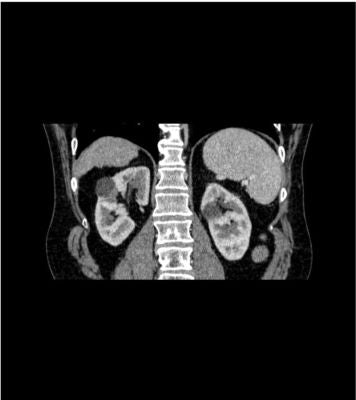

The phantom represents an abdomen after cholecystectomy with small clips. The liver has typical signs of cirrhosis and there is an inferior vena cava filter implanted at the level of the third lumbar vertebra. Both kidneys have cystic lesions and there is a small kidney stone on the left side.

This phantom simulates a contrast medium-enhanced abdomen in portal venous phase. It covers the tenth thoracic vertebra to the third lumbar vertebra.